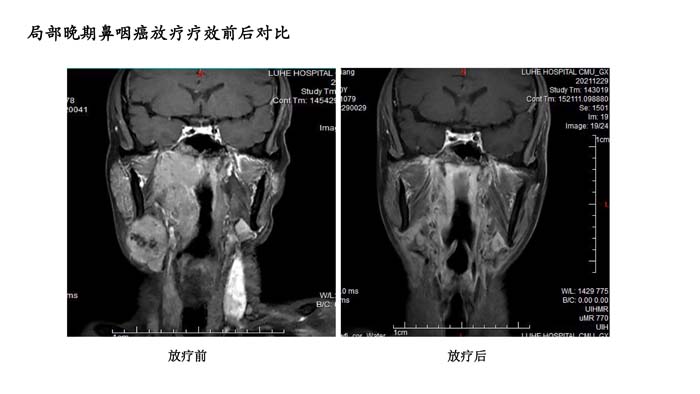

上一篇: 局部晚期鼻咽癌放疗疗效前后对比2